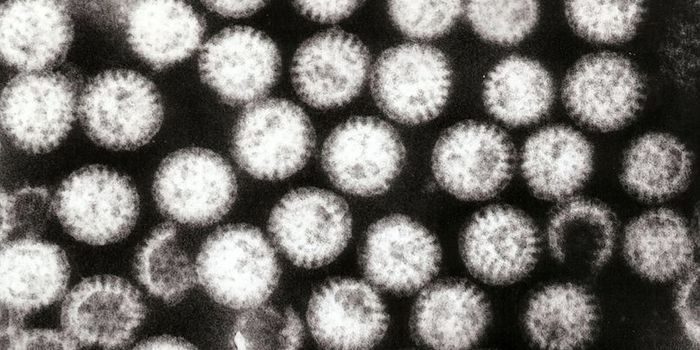

AUG 12, 2017

Microbiology

Study indicates the efficacy of the rotavirus vaccine - it likely resulted in 380,000 fewer hospitalizations of young ki